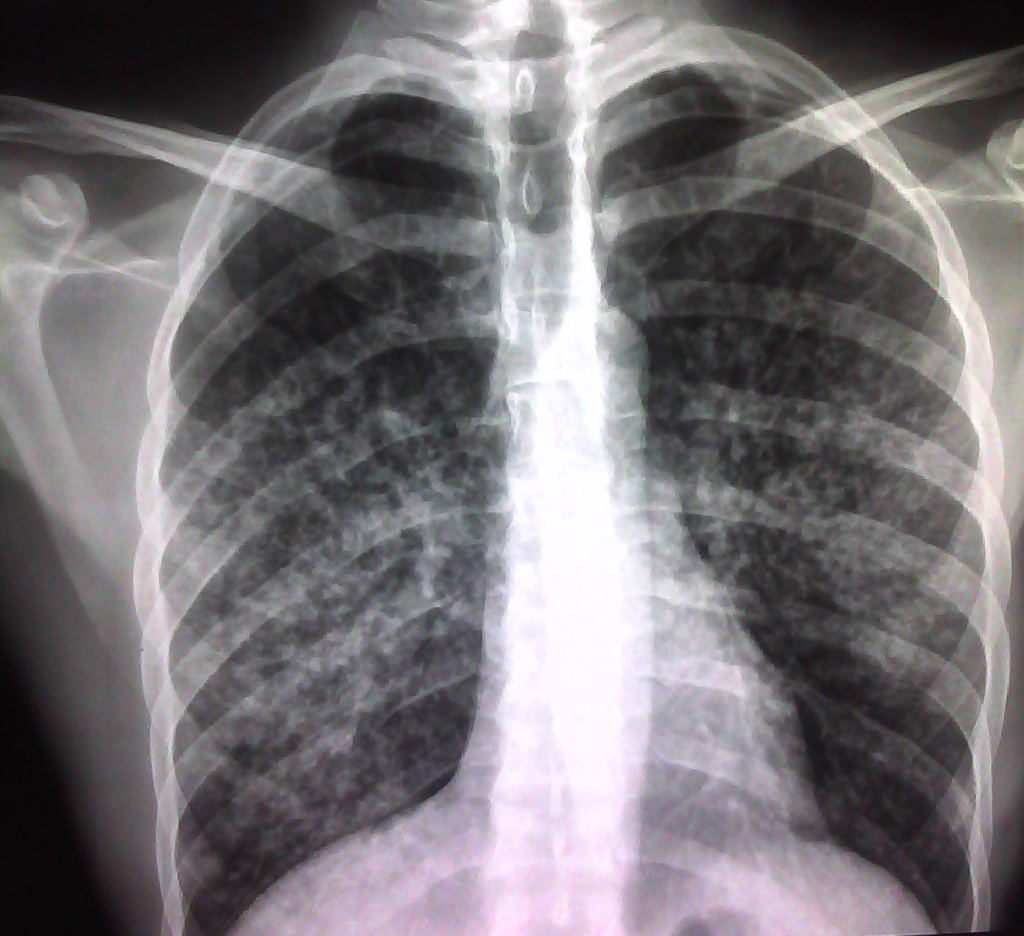

En concreto, los investigadores han estudiado un tipo de adenocarcinoma de pulmón cuyos pacientes tienen una mutación en el gen KRAS, el cáncer más perjudicial de todos los de ese órgano.